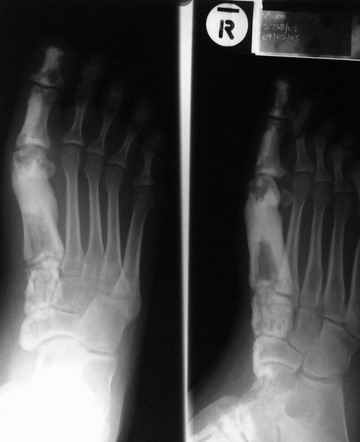

Кто шустрый - при какой патологии встречается так называемые "суставы Шарко"?Второе приобретение доктора Эмануэла мне понравилось своим романтическим названием: Candle bone - <кость-в-виде-оплывающей-свечи> : Просто редкая патология:

VR>Второе приобретение доктора Эмануэла мне понравилось своим романтическим названием: Candle bone - <кость-в-виде-оплывающей-свечи> : Просто редкая патология:

Мелореостоз

Под названием "мелореостоз" описано около 50 случаев врожденного заболевания скелета, выражающегося в совершенно

своеобразном одностороннем остеосклерозе костей одной только конечности. Можно не сомневаться в том, что

мелореостоз встречается далеко не редко; мы наблюдали свыше 20 случаев. Вполне естественно, что отдельные новые

казуистические наблюдения, не вносящие в науку никаких новых фактов и не возбуждающие новых мыслей и обобщений,

остаются неопубликованными.

Остеосклероз при этом заболевании захватывает не всю кость по окружности, а простирается слегка волнистой

полосой вдоль длинной оси конечности (рис. 223, К), переходя через линию суставов на другие кости. Таким образом,

может оказаться пораженной целая верхняя или нижняя конечность или больший или меньший ее периферический участок,

например, часть лопатки, полуцилиндр плечевой кости, часть цилиндра лучевой кости и скелет II пальца вместе с

лежащими по этой оси участками запястных костей или же часть - медиальная или латеральная - бедренной,

болынеберцовой кости с продолжением и расширением процесса на предплюсневые и плюсневые кости и соответствующие

по длиннику фаланги одного или нескольких, но никогда не всех пальцев. Описавшие эту болезнь в 1922 г. Жоани

(Joanny) и Лери (Leri) сравнивают остеосклеротические полосы с картиной, напоминающей стекающий со свечи и

застывающий стеарин или воск, отсюда и название "мелореостоз" - "стекающая вдоль конечности кость".